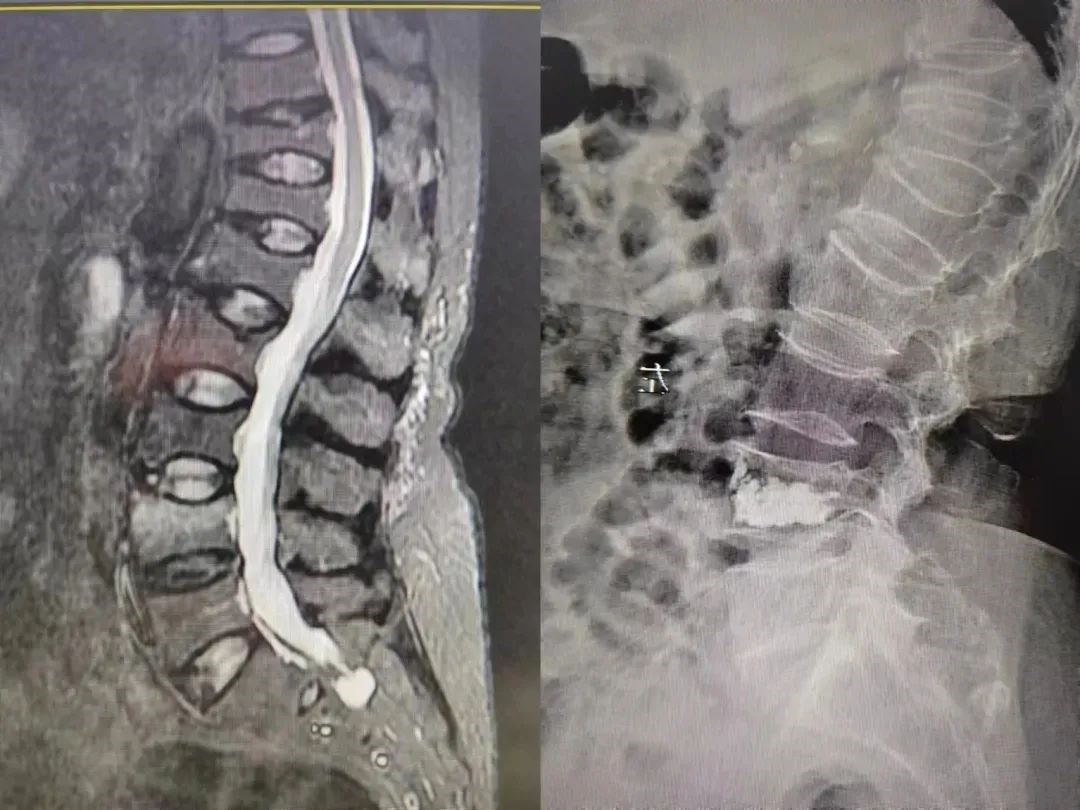

病例二

64岁女性患者,因腰背部疼痛,伴屈伸活动受限,床上翻身、久站后疼痛加重明显,特来我院就诊,骨二科团队经过经辅助检查后明确诊断为腰4椎体压缩性骨折,需尽快手术。

骨二科团队告知患者及家属病情及治疗方案,向患者及家属详细交代手术危险性及并发症,积极完善术前相关检查后,骨二科团队在局麻下行经皮穿刺腰4椎体球囊扩张成形术。

骨二科团队不仅在专业手术中展现出了高超的技术和精湛的操作,同时也给患者带来了信心和希望。手术后,在院康复期间一直耐心地与患者交流,让患者感受到了医生们的关爱和温暖,在经过一段时间的治疗后,患者已康复出院。